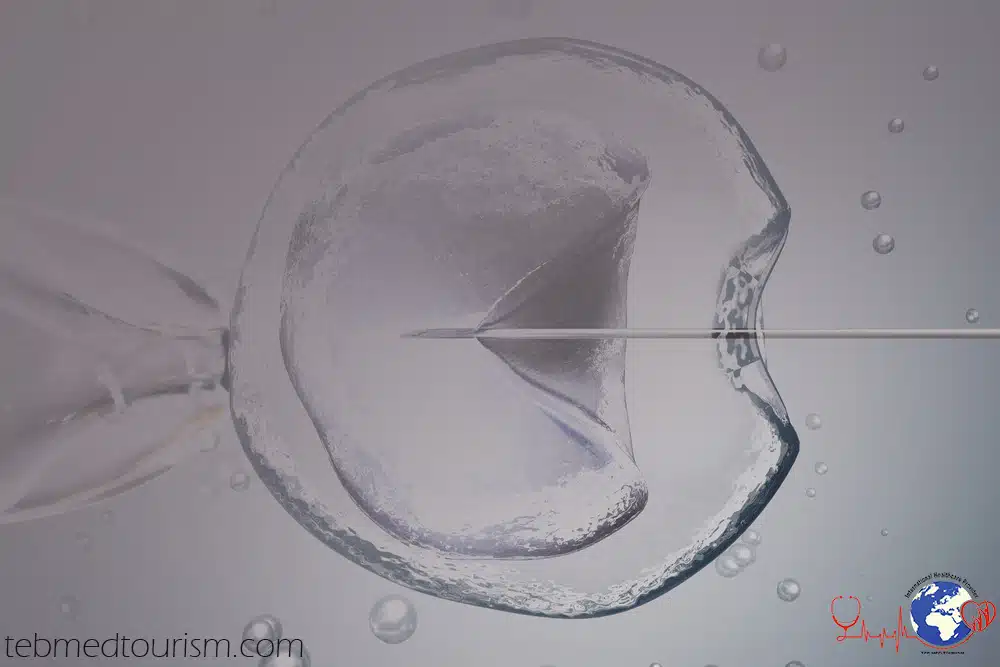

Yumurtahüceyrələri günün birinci yarısında götürürlər. Bu prosedura axırıncı hormonal inyeksiyadan 34-36 saat sonra aparılır. Həmin vaxt ərzində injeksiya edilmiş İQH yumurtahüceyrəni yetişmiş hala gətirir və follikul mayesinə ifraz edir. Yumurtahüceyrələr follikul mayesinin sorulması yolu ilə yumurtalıqlardan götürülür. Bu əməliyyat ultrasəslə idarə olunan nazik iynəni uşaqlıq boynundan salmaqla həyata keçirilir. Əməliyyat zamanı Sizə güclü ağrıkəsici və sakitləşdirici dərmanlar veriləcəkdir. Adətən bu əməliyyat ağrısızdır. Çox nadir hallarda yumurtahüceyrələr narkoz altında götürülür. Yumurtahüceyrənin götürülməsi, follikuların sayından asılı olaraq 10-20 dəqiqə çəkir. Yumurtahüceyrələr götürüldükdən sonra tibb bacısı Sizi istirahət otağına aparacaq. Bir və ya daha artıq saat istirahətdən sonra, müalicənin davamı haqqında təlimat alaraq evə gedə bilərsiniz. Sakitləşdirici dərman Sizin reaksiyanızı aşağı sala bilər. Buna görə də sükan arxasında əyləşməyi məsləhət görmürük. Ehtiyac varsa Siz və ya yoldaşınız həmin gün üçün, xəstəliyə görə işdən icazə ala bilərsiniz. Embrioloq mikroskop vasitəsilə follikul mayesindən yumurtahüceyrələri taparaq, Petri kasasına yığır. Yumurtahüceyrələr xüsusi isti dolabda, orqanizmdəki şəraiti imitasiya edən qidalı mühitdə inkişaf edirlər. Yumurtahüceyrələr ətraf mühitin temperaturunun və turşuluğunun (PH) dəyişməsinə çox həssasdırlar. Ona görə də yumurtahüceyrələrlə iş, qızdırıcılarla təchiz edilmiş xüsusi otaqda, yüksək sürətlə aparılır.

Spermanın miqdar və hərəkətlilik kimi keyfiyyət göstəriciləridən asılı olaraq mayalandırma in vitro(İVF) və ya mikromayalandırma (İCSİ) yolu ilə aparılır. Mayalandırma üçün spermadan normal formaya malik və daha çox hərəkətli spermatozoidlər seçilərək ayrılır. Mayalandırma yumurtahüceyrə götürüldükdən bir necə saat sonra aparılır.

İVF – in vitro (orqanizmdən kənar) mayalandırma

Spermatozoidlərin sayı, hərəkətliliyi və quruluşuna görə sperma normaldırsa və ya normadan az fərqlidirsə mayalanmanı ənənəvi in vitro üsulu ilə aparmaq olar. Bu üsulda təmizlənmiş sperma yumurtahüceyrə olan kasaya əlavə edilir. Spermatozoidlər yumurtahüceyrəyə doğru hərəkət edərək onun səthinə yapışır və beləliklə mayalanma baş verir.